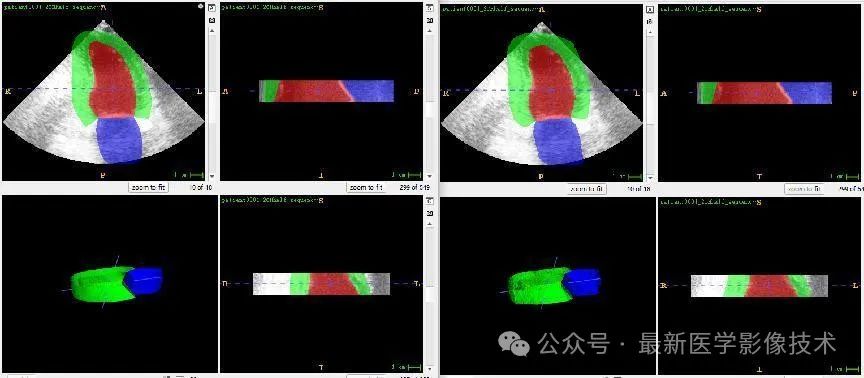

4、验证集部分分割结果

左边是金标准结果,右边是预测结果。